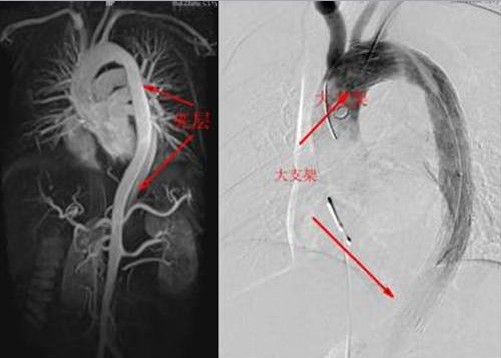

12月2日上午10時(shí),完善各項(xiàng)術(shù)前準(zhǔn)備工作后,患者被送進(jìn)了介入診療中心手術(shù)室。心血管醫(yī)學(xué)中心的專家們迅速為患者實(shí)施了主動(dòng)脈造影術(shù),發(fā)現(xiàn)患者撕裂的主動(dòng)脈竟有兩個(gè)破口!如果不封住這兩個(gè)破口,血流將會(huì)從破口不斷流入撕裂的假腔并導(dǎo)致假腔內(nèi)壓力越來越大,而當(dāng)假腔的壓力達(dá)到一定程度后就有可能完全破裂而導(dǎo)致大出血死亡。因此,如何封住這兩個(gè)破口就成了挽救該患者生命的主要目標(biāo)。以前完成此目標(biāo)必須進(jìn)行開胸手術(shù),將一種人造的血管縫合在夾層的內(nèi)表面從而堵住破口。而心血管醫(yī)學(xué)中心的專家們采用當(dāng)今最先進(jìn)的技術(shù),甚至不需股動(dòng)脈切開,僅僅在大腿根部的股動(dòng)脈打一個(gè)小孔即完成了這一高難度的手術(shù)!他們通過這一小孔建立了一個(gè)輸送通道,并順著這一通道先后將兩個(gè)大覆膜支架由遠(yuǎn)及近釋放到患者撕裂的主動(dòng)脈內(nèi),并牢牢地封住了兩個(gè)撕裂的破口,整個(gè)手術(shù)過程不到2個(gè)小時(shí)!該手術(shù)的成功,標(biāo)志著我市心臟大血管疾病的診療技術(shù)水平又邁上了一個(gè)新的臺(tái)階!